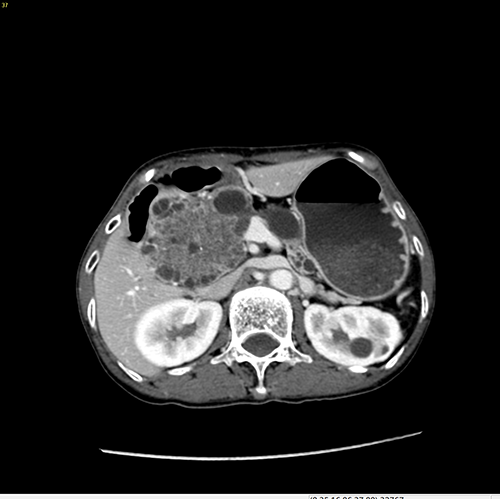

胰头囊腺瘤---胰十二指肠切除